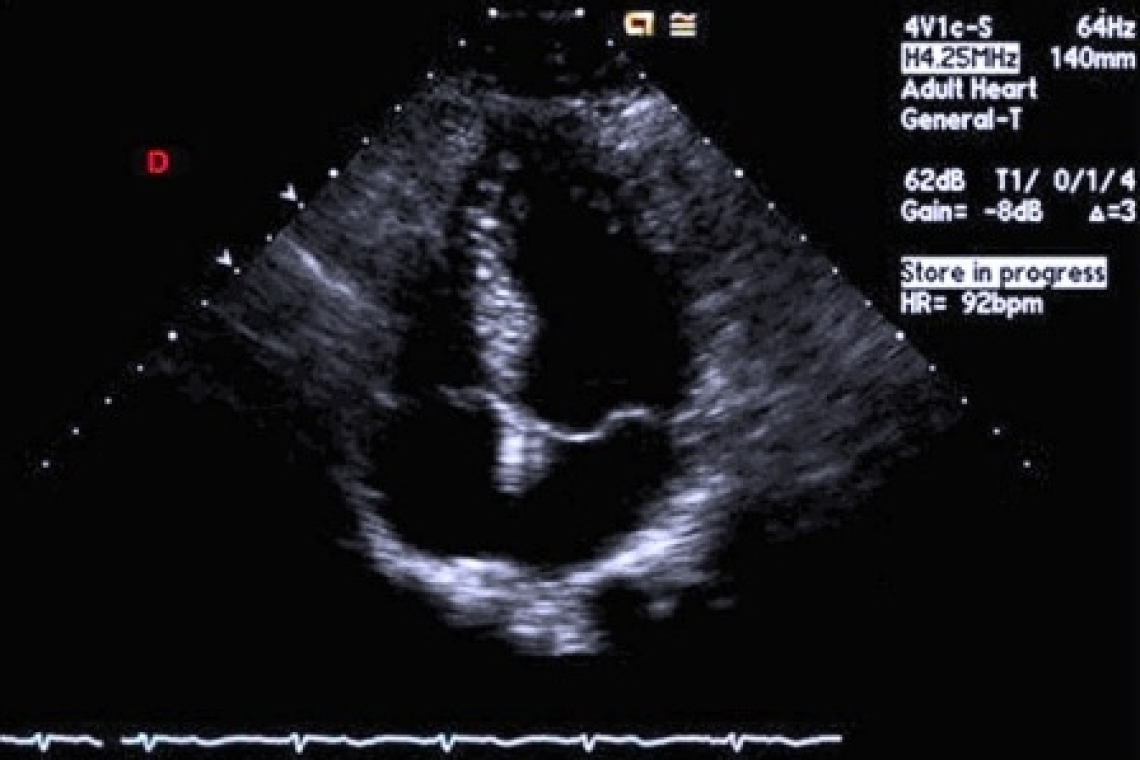

Такие симптомы во время беременности, как одышка при физической нагрузке, ортопноэ, отеки голеней на уровне лодыжек и сердцебиение, также являются признаками сердечной недостаточности, но могут возникать у здоровых женщин, как проявление функциональной – временной недостаточности. Практически у всех беременных женщин выслушиваются мягкие, систолические, физиологические шумы сердца. Выслушиваются они вдоль левого края грудины и обусловлены функциональным легочным стенозом из-за увеличения объема крови протекающего через клапан легочного ствола. Также возможны следующие физиологические изменения: расширение яремных вен на шее, хрипы в базальных отделах легких, видимый верхушечный толчок в 3-4 межреберье по средней ключичной линии, усиление тонов сердца, периферические отеки. Диастолические шумы (мур-мур) во время беременности встречаются редко, несмотря на увеличение кровотока через атриовентрикулярные клапаны. Наличие диастолических шумов должно подтолкнуть доктора к дальнейшему обследованию пациента для исключения более серьезной сердечной патологии. Интенсивные систолические шумы, их непрерывное повторение или же сочетание этих шумов с патологическими симптомами или электрокардиографическими изменениями – так же требуют дальнейшего обследования, в частности эхокардиографии. Электрокардиография как простой, недорогой метод обследования поможет определиться с необходимостью дальнейшего обследования. Во время беременности возможно смещение электрической оси сердца вправо или влево, увеличение амплитуды зубца R в отведениях V 1 и V 2 , инверсия зубца Т в отведении V 2 , снижение амплитуды зубца Q и инверсия зубца Р в отведении III. У 73-93% беременных возможно развитие аритмии.